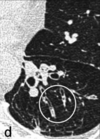

121

TC en bronquiectasia

Mejor método diagnóstico * Engrosamiento de pared bronquial * Impactación mucoide * Atrapamientode aire (mosaico) * Agrandamiento de arterias bronquiales

Bronquiectasia